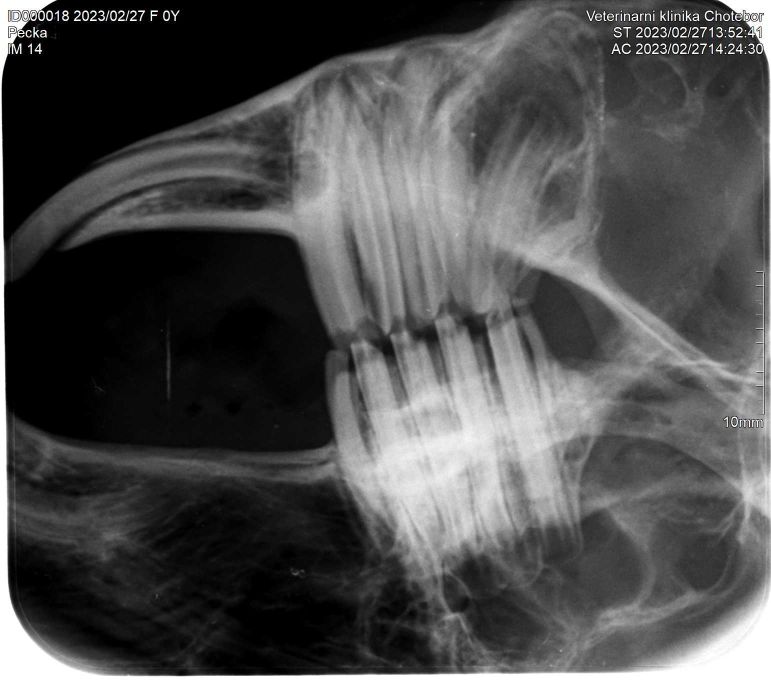

** RTG vyšetření hlavy: ** RTG vyšetření hlavy by mělo být provedeno

pokaždé, pokud je to možné. Může pomoct odhalit okem neviditelné

problémy lehce přehlédnutelné během základního vyšetření. Díky RTG

vyšetření posoudíme kostní podklad hlavy a celou délku zubů. Na našem

pracovišti se standardně využívá dentální rentgen a kombinace

extraorálních a intraorálních projekcí. Dentální rentgen nám umožňuje

přesně zacílit vyšetřovanou oblast a méně zatěžovat okolní prostředí

rentgenovým zářením. Pro pacienta i pro personál je toto vyšetření

šetrnější a zároveň nabízí větší výtěžnost. Používáme velmi

malé senzory s vysokým rozlišením pro nepřímou digitalizaci. Výsledný

obraz je po nasnímaní digitalizován a zobrazen na monitoru PC pro další

interpretaci. U některých pacientů je RTG vyšetření nedostatečné a

majitelům je navrženo referování na specializované pracoviště

s doporučením pro CT vyšetření oblasti hlavy pacienta. Jedná se o malé

množství pacientů s velmi pokročilým onemocněním.